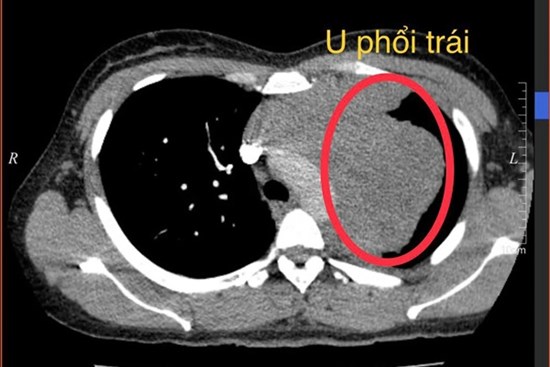

Chị Hà (*), 34 tuổi tại Phú Thọ, đi khám sức khỏe tình cờ phát hiện mắc ung thư phổi trái xâm nhập trung thất và ngực trước.